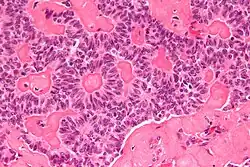

| Micrograph of a sex cord tumour with annular tubules. H&E stain. | |

It has a distinctive appearance under the microscope, from which it derives its name.

Intermediate magnification

High magnification